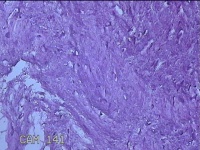

右膝前瘢痕增生组织

性别

女

年龄

38岁

临床诊断

右膝前瘢痕增生

一般病史

右膝前外伤后瘢痕增生4年余。

标本名称

大体所见

灰白粉红色组织6.5x5x1.8cm一块,表面光滑,切面灰白粉红色,质软。